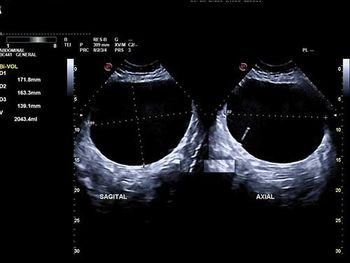

Challenge your diagnostic skills: What's causing this woman's pelvic discomfort?

Challenge your diagnostic skills: What's going on with this umbilical cord?